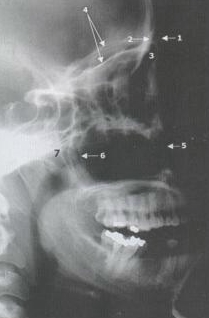

Lateral View

• Frontal Sinus

• Maxillary Sinus

• Pterygoid (Le Fort Fracture)